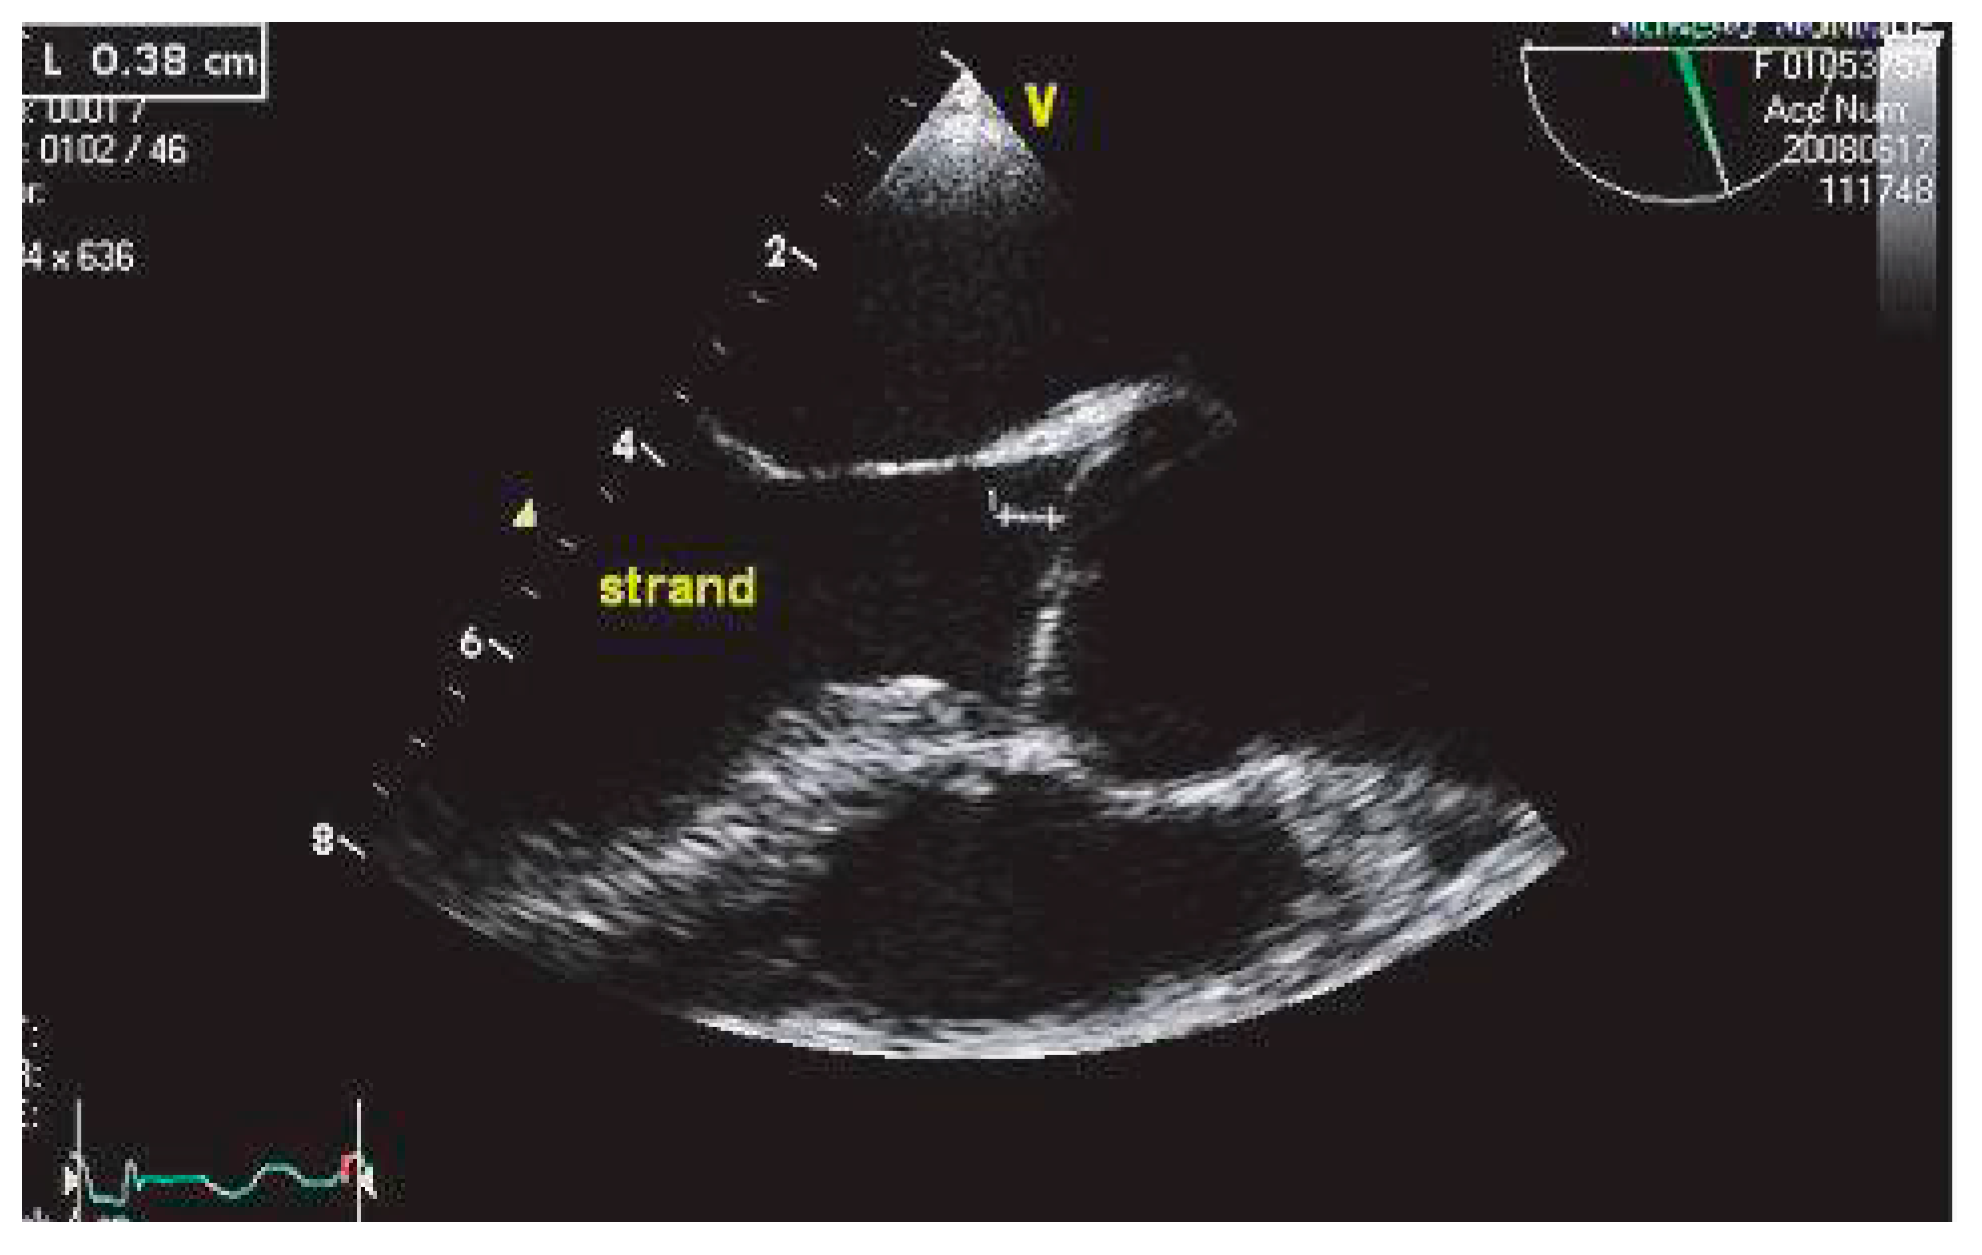

Filaments valvulaires ou strands

Les filaments valvulaires ou «excroissance de Lambl» décrits initialement par les anatomistes sont diagnostiqués par la seule ETO (Figure 8). Il s’agit de filaments mobiles, s’insérant de façon élective sur la face auriculaire de la valve mitrale et la face ventriculaire des valves semi-lunaires aortiques, la localisation valvulaire droite étant exceptionnelle. La prévalence des filaments valvulaires augmente avec l’âge, pour être quasi constante après 80 ans dans les séries anatomiques [71]. Un lien a été suggéré entre la présence de filaments valvulaires et le risque d’AIC [72]. Cependant, l’étude de suivi de la cohorte française a montré qu’il n’y avait pas d’augmentation du risque de récidive d’infarctus cérébral [73]. La présence de filaments valvulaires pourrait donc ne constituer qu’un marqueur du risque d’infarctus cérébral, associé dans tous les cas à un faible risque de récidive. Il faut cependant différencier les filaments valvulaires sur valves natives des filaments valvulaires décrits chez les patients porteurs de prothèses valvulaires, plus souvent mécaniques que bioprothèses, avec une fréquence évaluée respectivement à 27% et 8% [p = 0.03) dans la série d’Orsinelli [74]. Il s’agit dans ce dernier cas de thromboses non obstructives, associées à un risque accru d’embolie artérielle, en particulier dans la phase postopératoire. Un traitement anticoagulant adapté contribue à réduire ce risque; dans ce contexte, le contraste spontané dans l’oreillette gauche est un facteur favorisant, de même que la fibrillation auriculaire.

Figure 8. Filament valvulaire (strand) sur la valve aortique.